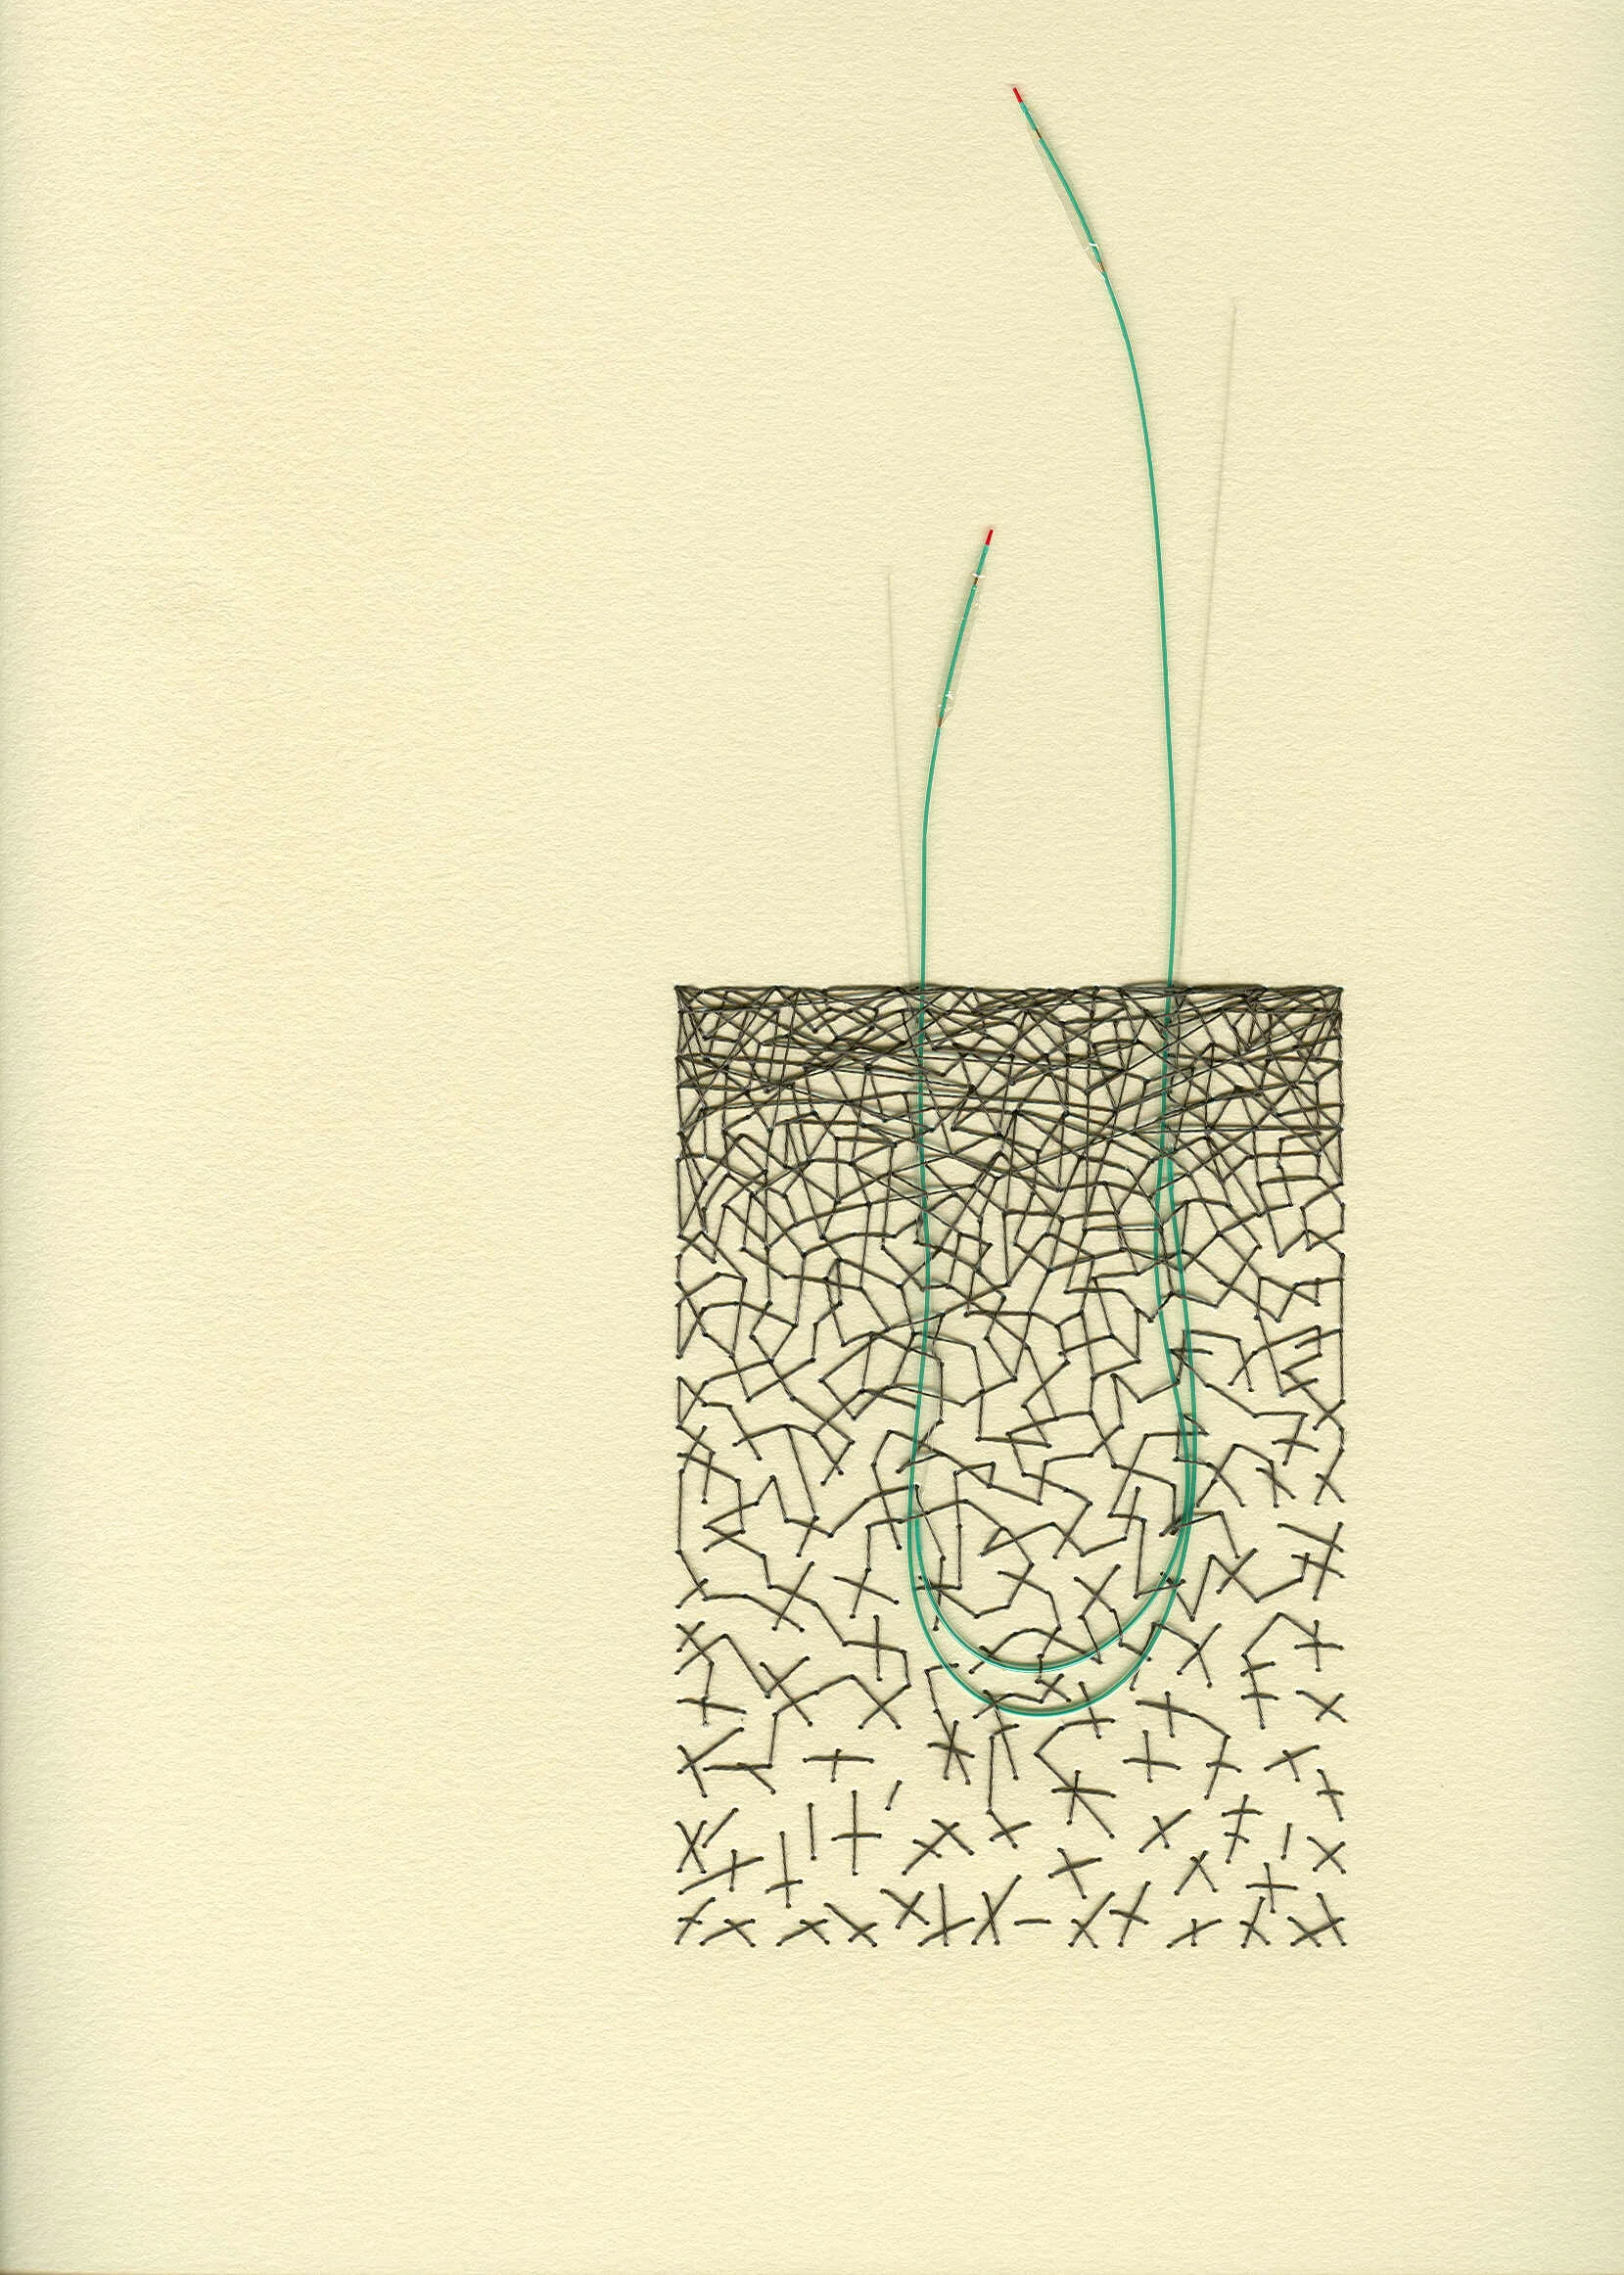

I’ve also had the pleasure of creating artwork for another corporate headquarter building based in MN. Boston Scientific commissioned me to create found object works that featured products which they created. You’ll see below some of those that feature angioplasty ports and balloons.

Chaos 4